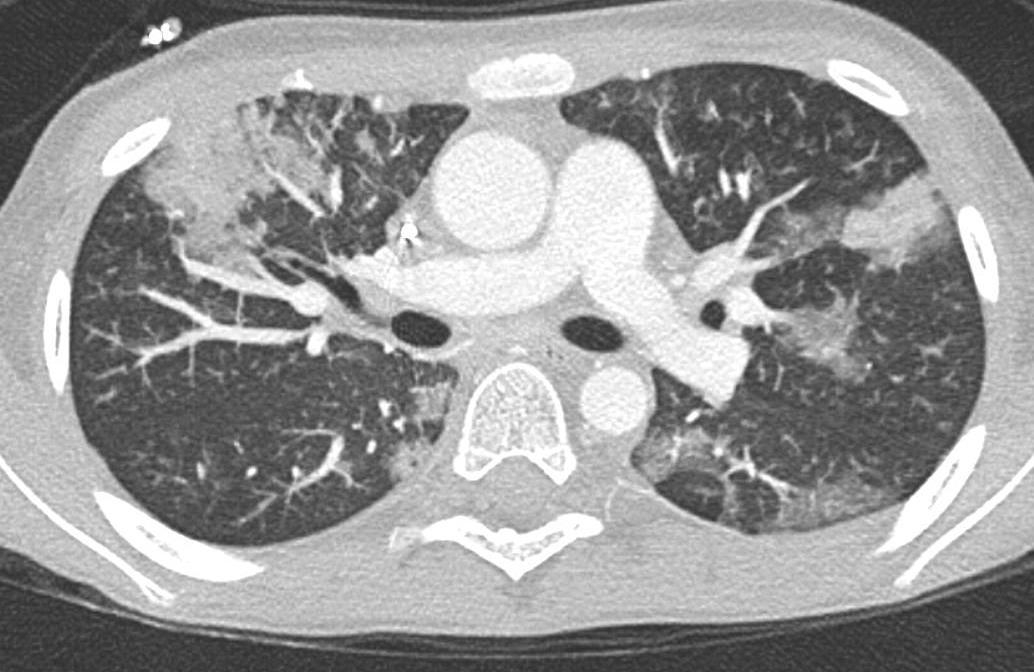

Acute Pediatric COVID-19: CT

Progressive: Diffuse GGO

Developed: Consolidation

Imaging of Covid 19 infection in children

Early: "Halo" sign

Local infection Surr vasc congestion

Apicale sinistraa Medio -Basale sinistra

Basale sinistra Basale sinistra